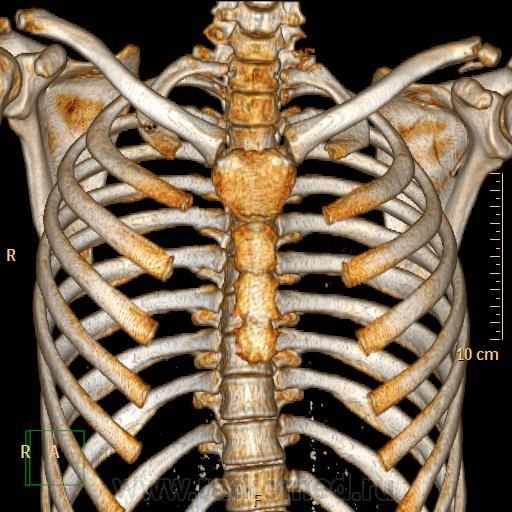

Компьютерная томография (КТ) грудной полости

Травма органов грудной клетки на примере клинических случаев